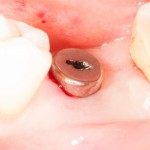

Всё. Имплантат установлен:

Еще раз проверяем глубину погружения — с помощью зонда измеряем расстояние от импланта до поверхности слизистой оболочки — оно должно совпадать нашими замерами толщины десны. Ну и, проверяем, что имплантат со всех сторон окружен костной тканью:

Можно поставить формирователь десны:

Операция закончена. Швы не нужны.

Конечно, имплантация и разрезы с помощью мукотомов — это немного больше возни и более сложный контроль за процессом. Однако, мы добились минимальной раны и, следовательно, минимальной инвазивности вмешательства.